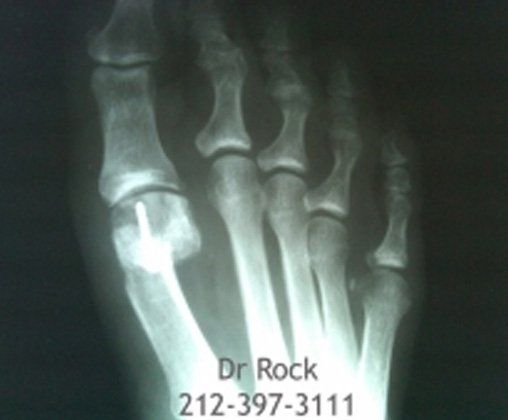

Take a look at our x-ray pictures of our recent footwork and see how your feet can benefit.

Whether you want to improve the look of your feet or need to relieve pain,

you can find out the best option for you with our FREE phone consultation.